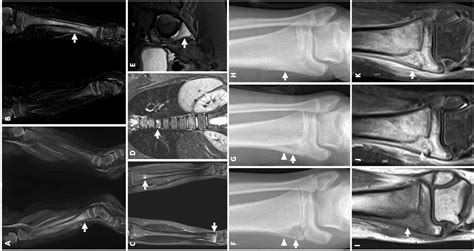

Diagnostic Approach and Imaging

Diagnosing Chronic Multifocal Osteomyelitis is a process of exclusion. Because there is no single laboratory blood test that confirms the diagnosis, physicians rely on a combination of clinical findings, imaging, and, in some cases, a bone biopsy to rule out other more serious conditions like malignancy or bacterial osteomyelitis.

MRI (Whole Body) The gold standard for identifying multifocal lesions without radiation exposure.

X-rays Useful for evaluating bone damage, though often normal in the early stages.

💡 Note: A whole-body MRI is highly recommended by specialists to identify asymptomatic lesions that might otherwise go undetected.